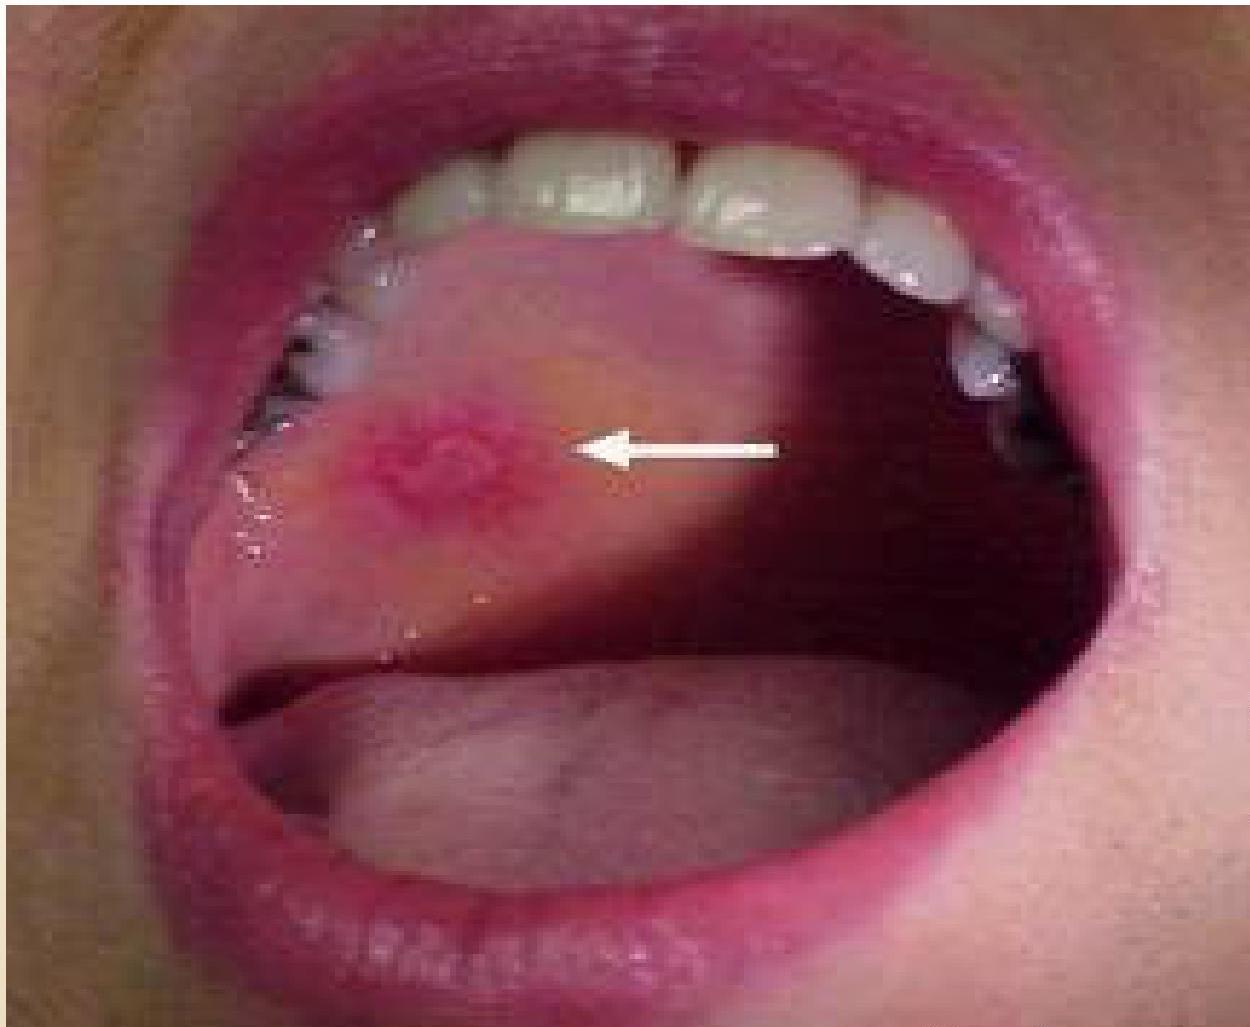

- Discoid Lupus Erythematosus (DLE): (See image)

- Other: Photosensitivity, diffuse maculopapular rash, cutaneous vasculitis, oral/nasal ulcers.

(Left: Discoid Lupus Rash. Right: Malar Rash)

- 6) Mouth: Ulcers

- 7) Skin rash: Skin is affected in 85% patients Butterfly rash Discoid rash Butterfly rash is characteristic of SLE SLE rash gets worse in sunlight (photosensitive)

Sometimes discoid skin lesions are seen

SKIN RASH IN SLE ⇒ Butterfly rash on the face a) involves the cheeks, b) crosses over the nasal bridge c) no involvement of the nasolabial fold d) May be slight pain or HAKKA

Four SLE criteria are dermatologic:

- Photosensitivity

- Discoid lesions

- Oral ulcerations

- Malar rash

-

Photodistributed

Often scaly, scarring

Spares nasal creases (unlike seborrheic dermatitis)

May mimic rosacea